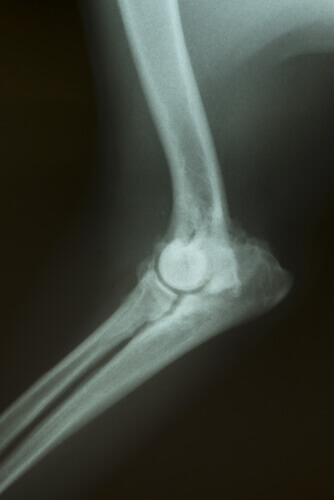

Joints are what join the bones of our body to one another, which move thanks to articular cartilage. This cartilage covers the joints and allows for mobility between the bones.

In the case of canine arthrosis, this cartilage ages and begins to fail, losing lubrication and becoming malnourished. As a result, pain develops when animals try to move. This illness is degenerative and has no cure. However, there are some ways to provide some relief from the symptoms.

- A dog doesn’t want to climb stairs. This may be one of the most painful actions for a dog with arthrosis to perform. That’s because the knees are the joints that suffer the most because they bear the animal’s weight. Climbing stairs requires a great effort so, in an attempt to avoid this pain, the dogs may refuse to do so.